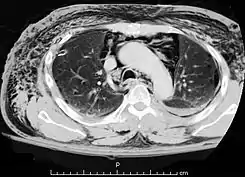

Una TAC que muestra aire en el mediastino